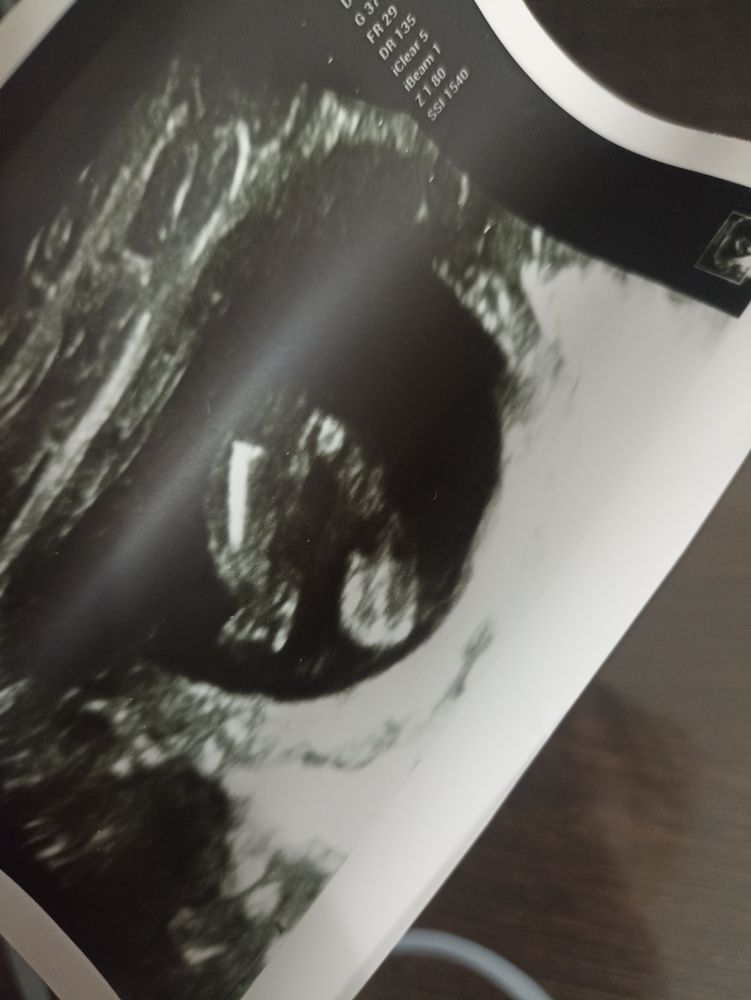

Елки, долго всматривалась, пока не поняла, что это ножки 😁 Я ни разу не специалист, но мне видится мужское начало там)) У дочи было не очень понятно, но выглядело не так, скорее было похоже на опухшую мошонку😁Может, конечно, я не туда смотрю, но я вижу стручок🙈

Валентина, или это кофейное зернышко и пуповина))

Валентина, узист сказала, если бы мальчик, то было бы ещё кое что видно) сказала, что девочка

По мне тут полосочка между ног ,но лучше бы у узиста спросили ,он лучше видит